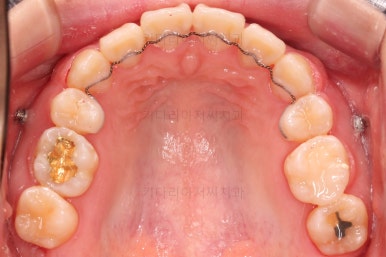

장치를 부착합니다.

이번 환자분이 선택한 장치는 엠파워 클리어라고 하는 자가결찰 세라믹 장치인데요.

철사를 묶는(결찰) cap이 장치에(자가) 달려있는 장치 중에 세라믹 성분으로 되어 심미성이 우수한 브라켓입니다.

대표적으로는 클리피씨 장치 등이 있습니다.

우선은 적응을 위해서 윗니만 장치를 부착하고요.

윗니도 어느새 치아를 뽑은 공간이 많이 줄었네요.

이 시점에서 약속한대로 중간평가를 해줍니다.

윗니는 아랫니가 뒤로 들어가는 만큼 더 뒤로 밀어야 되기 때문에 미니스크류를 이용해서 뒤로 당기기를 해줍니다.